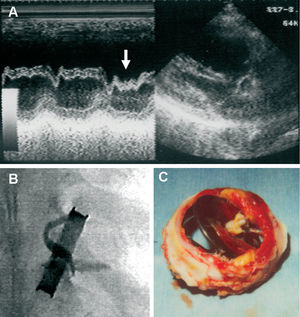

Una mujer de 56 años de edad fue admitida en urgencias tras un episodio sincopal. Catorce años antes, la paciente se había sometido al implante de una prótesis tricuspídea por anomalía de Ebstein con insuficiencia cardiaca congestiva (clase III de la NYHA) y regurgitación tricuspídea grave. Se había seleccionado una prótesis mecánica (válvula Medtronic-Hall® de 31 mm; Medtronic Inc., Minneapolis, Minnesota, Estados Unidos) por su tolerancia estructural y la edad temprana de la paciente. Desde dicha intervención, la paciente había tomado warfarina a diario para mantener un índice internacional normalizado entre 2,5 y 3,5. La ecocardiografía transtorácica mostraba movimientos posteriores intermitentes del tabique interventricular durante la diástole (fig. 1A). La cinerradiografía mostró un movimiento de apertura intermitente del disco de inclinación a pesar del ángulo de apertura patente (fig. 1B). Nos preocupaba que el movimiento posterior intermitente del septo interventricular estuviera causado por un flujo de entrada intermitente debido a un mal funcionamiento de la prótesis valvular. Se realizó una intervención inmediata para sustituir la antigua prótesis por una Hancock® bioprosthetic de 31 mm (Medtronic Inc.). La prótesis explantada estaba cubierta por un trombo (fig. 1C). Se sabe que la trombosis tardía es una complicación grave en el implante de prótesis tricuspídeas mecánicas. El movimiento posterior intermitente del tabique interventricular es poco habitual y fue un factor importante que nos condujo a diagnosticar una complicación seria en una prótesis tricuspídea mecánica.

Fig. 1.